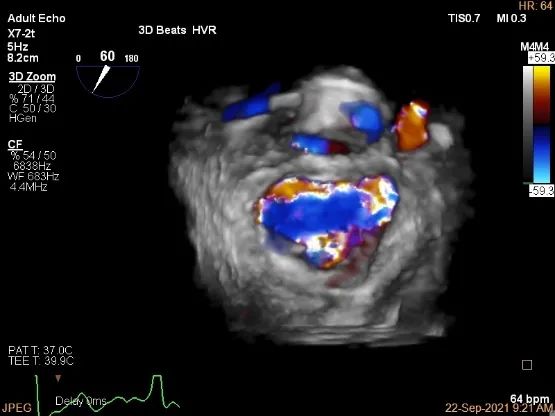

未见明确残余分流

三维评估两个夹子位置

3D-color再次确定未见残余分流

评估瓣口条件,平均跨瓣压差:4mmHg

夹子夹闭后,未见明确残余分流

3d确认夹子位置在P1区

3d-color确认残余分流情况